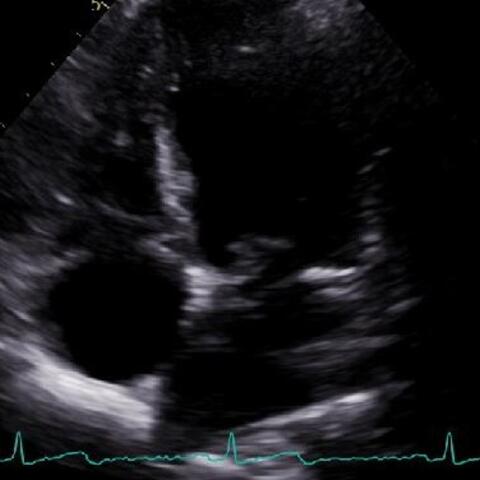

Dr. Jordan Strom and Dr. Tom Porter discuss the risks that come with underuse of contrast-enhanced ultrasound (CEUS), as well as its utility in clinical practice.